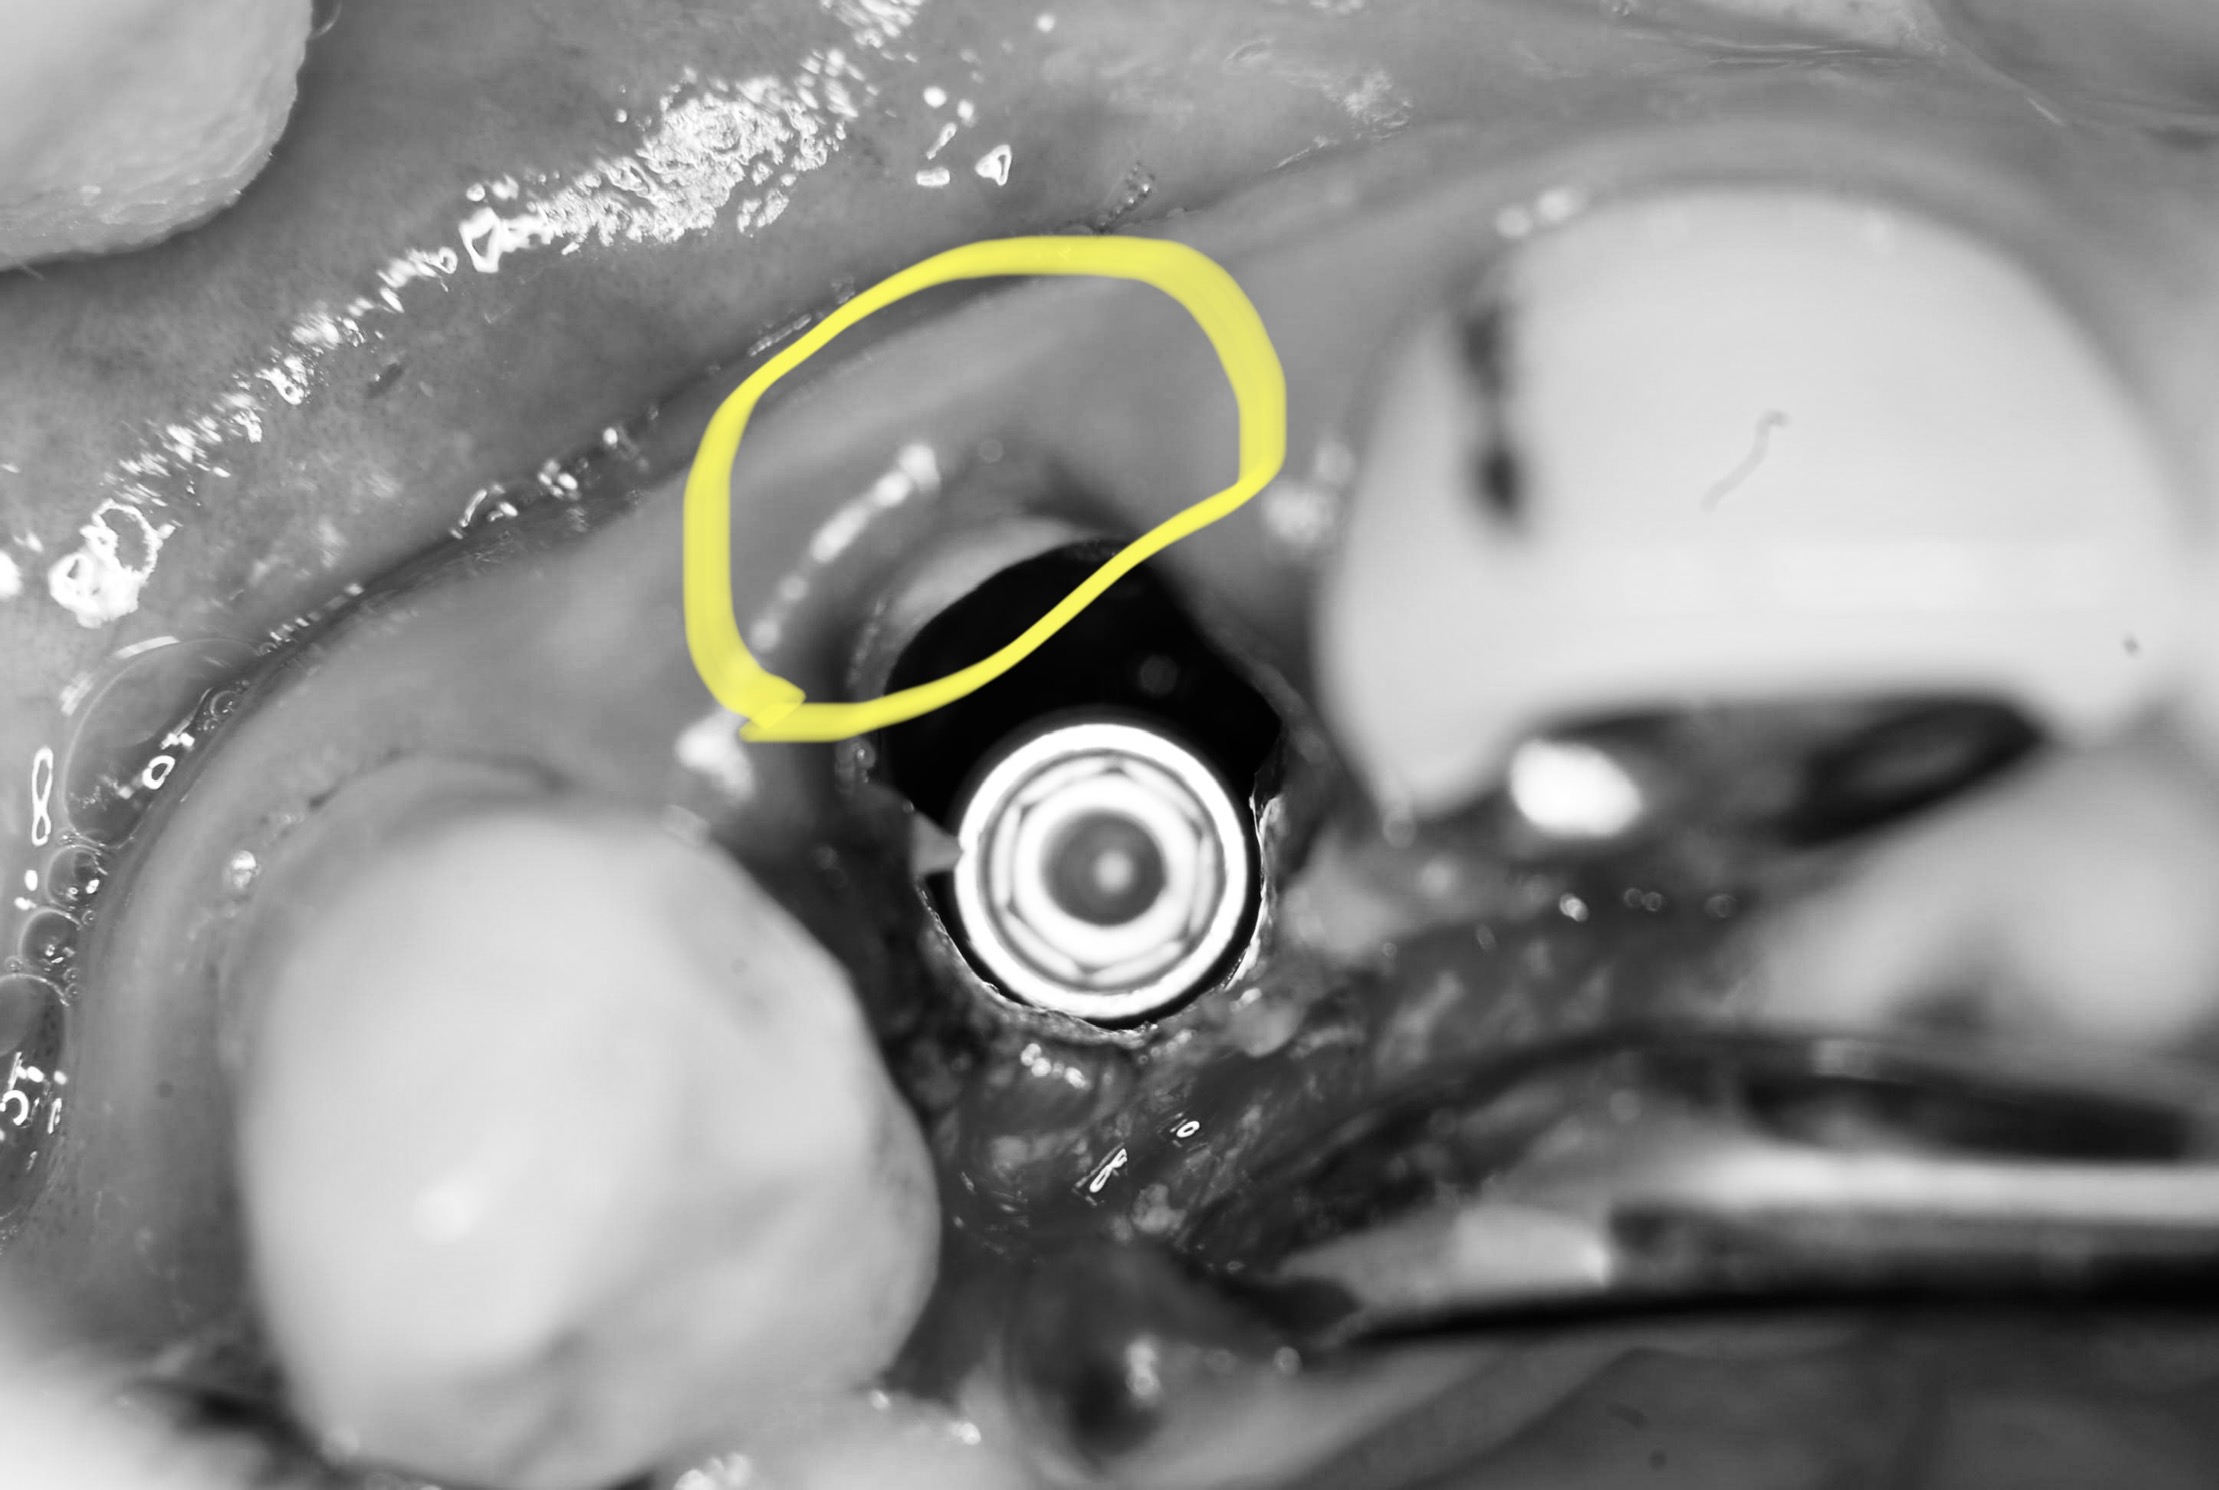

オペ途中に『破折した歯牙の唇側(外側)の歯質が一部使えそう‼︎』と判断し、歯根の一部を意図的に残し、ソケットシールド/ルートメンブレンテクニックに切り替えたそうです(ーー;)

(黄色の歯根一部がそれです)

この方法は最近雑誌にも色々な名称で掲載されてますが、狭窄歯列にならなく、食渣も起きず審美領域では出来るだけ保存したいですよね

組織を新しく作るより、いまあるものを保存して使う。天然歯の歯根の回りには『歯根膜』と言う血液が豊富な膜が付いています。全部抜いてしまうと周囲の組織が枯れて吸収が始まります。この膜を残す事で歯槽骨や歯肉の吸収を抑え天然歯なみの歯肉のボリュームを確保して審美的にも、腫れや痛みも軽減できインプラントオペの成功率が上がります(低侵襲かつ短期間で治療を終える要因に‼︎)